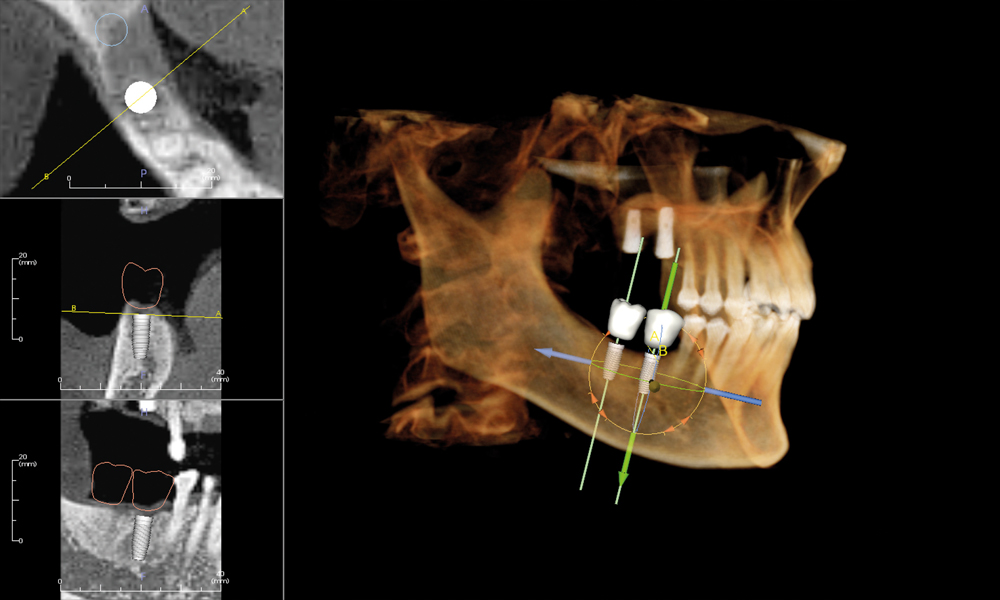

Undistorted, anatomically correct views of the jaws, teeth and facial bones along with cross-sectional (bucco-lingual), axial, coronal, sagittal, cephalometric and panoramic views are easily generated.

Three-dimensional images enable a level of anatomical accuracy and patient care not possible with 2-D technologies. With the addition of cone-beam CT technology in our office, our practice is committed to providing innovative, high-quality, patient care.